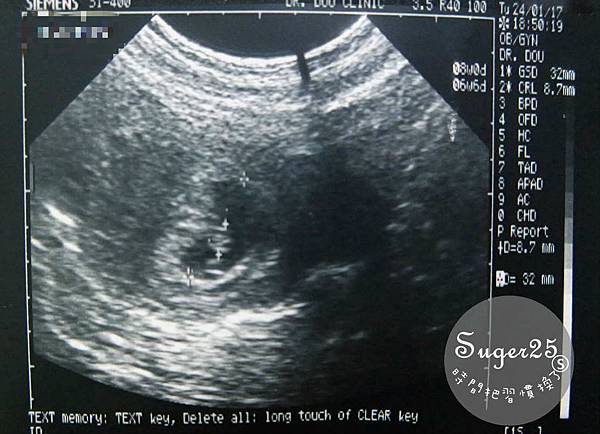

醫生說~有寶寶摟!!!已經幾周了~((我忘了

第一次看到寶寶超小的~還蠻到很感動,但自己知道~我當媽了!!!!!!!!!

這是10W的孩子~已經有看到身體&頭了!!!